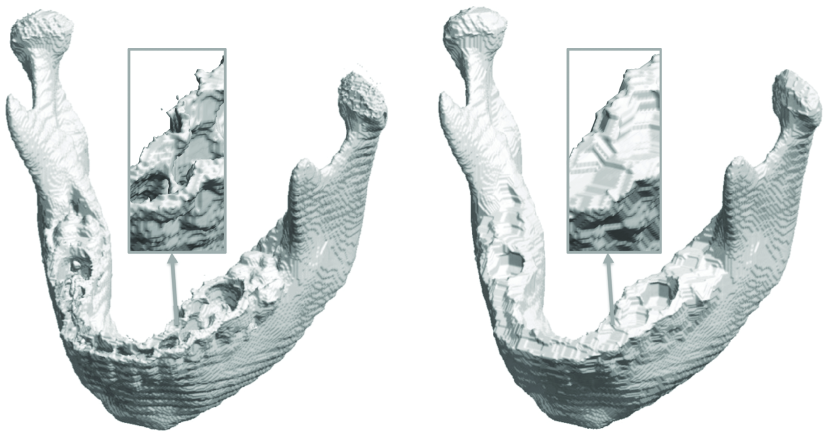

Note that for each triangle, there are three edges. For a closed surface topologically equivalent to a sphere, two adjacent triangles share the same edge. Hence, the total number of edges is . The relationship between the number of vertices and the triangles is . We simply need to compute the Euler characteristic as and check if it is 2 at the end. All binary volumes produced the topologically correct surfaces without an exception. Fig. 5 shows an example of before and after the topology correction.

Topological defects are often encountered in image reconstruction. For instance, since the mandible and teeth have relatively low density in CT, unwanted cavities, holes and handles can be introduced in mandible segmentation (Andresen et al., 2000). An example is shown in Figure 5 where the tooth cavity forms a bridge over the mandible. In mandibles, these topological noises can appear in thin or cancellous bone, such as in the condylar head and posterior palate (Stratemann et al., 2010). If we apply the isosurface extraction on the topologically defect segmentation results, the resulting surface will have many tiny handles (Wood et al., 2004; Yotter et al., 2009). These handles complicate subsequent mesh operations such as smoothing and parameterization. So it is necessary to correct the topology by filling the holes and removing handles. If we correct such topological defects, it is expected the resulting isosurface is topologically equivalent to a sphere. There have been various topological correction techniques proposed in medial image processing. Rather than attempting to repair the topological defects of the already extracted surfaces (Wood et al., 2004; Yotter et al., 2009), we can perform the topological simplification on the volume representation directly using morphological operations (Guskov and Wood, 2001; Yotter et al., 2009). The direct correction on surface meshes can possibly cause surfaces to intersect with each other (Wood et al., 2004).